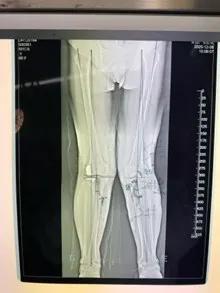

經(jīng)過詳細(xì)的體格檢查、影像學(xué)評估和三維重建,醫(yī)療團(tuán)隊確認(rèn)鮑奶奶的情況非常適合進(jìn)行膝外側(cè)單髁置換術(shù)。這種微創(chuàng)手術(shù)創(chuàng)傷小、恢復(fù)快,能夠最大程度保留膝關(guān)節(jié)的自然結(jié)構(gòu)和功能。

手術(shù)當(dāng)天,骨科團(tuán)隊采用微創(chuàng)切口,僅約8厘米,遠(yuǎn)小于傳統(tǒng)全膝關(guān)節(jié)置換手術(shù)切口。術(shù)中精準(zhǔn)定位,僅置換病變的膝關(guān)節(jié)外側(cè)間室。

手術(shù)使用了最新的單髁假體系統(tǒng),這種假體設(shè)計更符合人體工程學(xué),能夠更好地恢復(fù)膝關(guān)節(jié)的自然運(yùn)動軌跡。